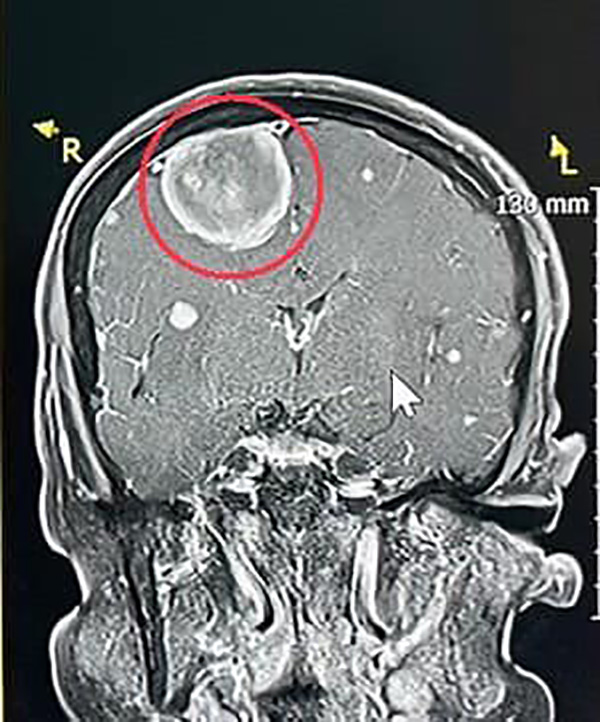

แพทย์เวรตรวจเบื้องต้น สงสัยอาการทางสมอง จึงส่งตรวจคลื่นแม่เหล็กไฟฟ้าสมอง พบเนื้องอกในสมองขนาด 3 เซนติเมตร จึงแนะนำให้นอนโรงพยาบาลวางแผนผ่าตัด ส่งปรึกษาแพทย์ผู้เชี่ยวชาญด้านประสาทศัลยศาสตร์ นัดผ่าตัดสมอง เอาก้อนเนื้อออกมาเป็นผลสำเร็จ หลังผ่าตัดผู้ป่วยฟื้นตัวได้เร็ว อาการอ่อนแรงค่อย ๆ ดีขึ้น ฟื้นตัวกลับมาใกล้เคียงปกติ